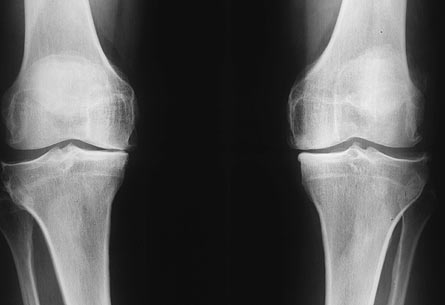

骨關節炎(OA)

骨關節炎(osteoarthritis,OA)是一種最常見的關節疾病。又稱退行性關節病、骨關節病。骨質增生,與人體衰老密切相關,多數老人都可能伴有骨質增生,自然容易得骨關節炎。臨床數據顯示,45歲以下人群骨關節炎患病率僅為2%,而65歲以上人群患病率高達68%。在醫生看來人到老年都患有不同程度的骨關節炎。主要是以關節軟骨的變性,破壞及骨質增生為特征的慢性關節病。本病的發生與衰老,肥胖,炎癥,創傷,關節的過度使用,代謝障礙及遺傳有相關性。

臨床表現:

1.疼痛、功能障礙

2.僵硬、不靈活

3.體征:關節間隙壓痛、四頭肌萎縮、關節積液等。

骨關節炎(OA)治療:

早中期:調整生活方式,物理治療,加強肌力鍛煉為主。包括適當休息,減肥,防止關節過度運動和過度負重,避免機械性損傷。疼痛劇烈者,可適當的加用非甾體類藥物減輕疼痛。

中晚期:手術治療,包括關節鏡手術,脛骨高位截骨,單髁關節置換術,全膝關節置換術等。